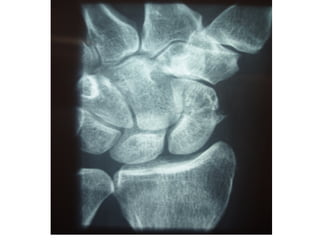

Radiography

 The 4 essential views (ie, PA, lateral, supinated and

pronated obliques) identify majority of fractures.

 The scaphoid view is a PA radiograph with the wrist

extended 30° and deviated ulnarly 20°. This view

helps to stretch out the scaphoid and is also used for

assessing the degree of scaphoid fracture angulation.

 A clenched-fist radiograph has also been useful for

visualization of the scaphoid waist.

Radiography  The 4essential views (ie, PA, lateral, supinated and pronated obliques) identify majority of fractures.  The scaphoid view is a PA radiograph with the wrist extended 30° and deviated ulnarly 20°. This view helps to stretch out the scaphoid and is also used for assessing the degree of scaphoid fracture angulation.  A clenched-fist radiograph has also been useful for visualization of the scaphoid waist.